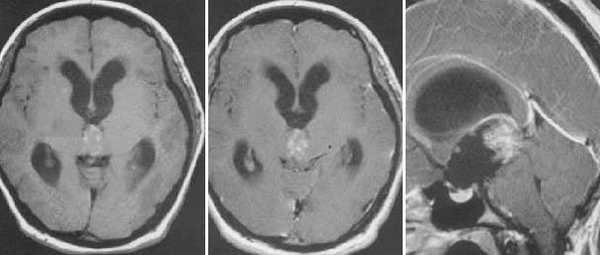

Диагностика: МРТ с контрастным усилением — стандартное исследование при опухолях этой локализации. При пинеоцитоме обнаруживают небольших размеров округлое образование в пинеальной области, с чёткими границами, активно и гомогенно накапливающее контраст и вызывающее компрессию пластинки четверохолмия. Для пинеобластомы характерны все признаки злокачественной быстро прогрессирующей опухоли (инфильтративный характер роста, гетерогенный сигнал с признаками некроза и кровоизлияний, большие размеры, субарахноидальные метастазы).

Пинеоцитома. На Т2 ВИ опухоль состоит из двух участков разной интенсивности МР-сигнала: высокой в передних отделах и низкой в задних. Четкость и линейность перехода свидетельствует о кистозном характере строения опухоли. Различия интенсивности МР-сигнала от жидкости в передних и задних отделах опухоли обусловлены эффектом «седиментации» белковых компонентов (вероятнее компонентов крови), опускающихся вниз при положении головы пациента на затылке.

Пинеоцитома. МРТ в режиме Т2 и Т1 выявляется солидного строения опухоль задних отделов III желудочка мозга. На фоне в/в контрастирования определяется выраженный и достаточно гомогенный характер контрастирования опухоли.

Пинеобластома. В режиме Т2 и Т1 выявляется опухоль задних отделов III желудочка мозга с развитием окклюзионной гидроцефалии. В строме опухоли небольшой участок подострого кровоизлияния. После в/в контрастирования опухоль интенсивно и достаточно гомогенно накапливает контрастирующее вещество.